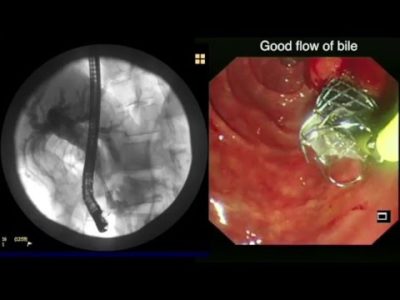

This animation focuses on two approaches in the treatment of pancreatic cancer: curative and non-curative (palliative), as well as its long-term outcomes.... Learn More